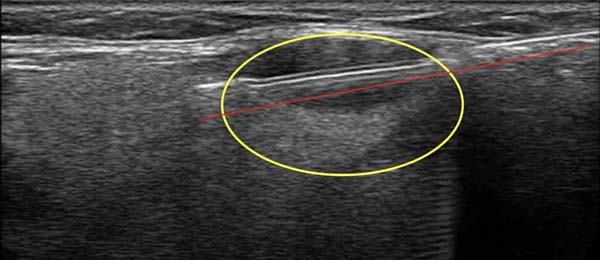

超声介入是在实时超声监控和引导下,完成临床需要的各种脏器或肿瘤的穿刺活检、造影、抽液、置管、注药或消融治疗等一系列的操作,满足临床诊断和治疗的需要。在穿刺过程中,超声影像能实时动态监控穿刺的目标、路径、取材过程,如下图为颈部肿大淋巴结的穿刺活检图,椭圆形黄色圈内是超声显示的肿大淋巴结,与红色箭头平行的白色亮线是超声影像实时显示的穿刺针。

正是由于超声引导穿刺活检的全程实时监控,因此可以有效避开大的血管和重要组织器官,使得这项技术具有了很高的精准度和安全性。